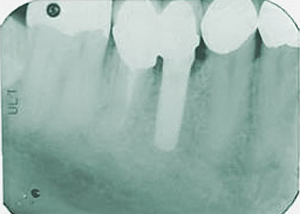

-8-上下・18本の土台のついたレントゲン所見